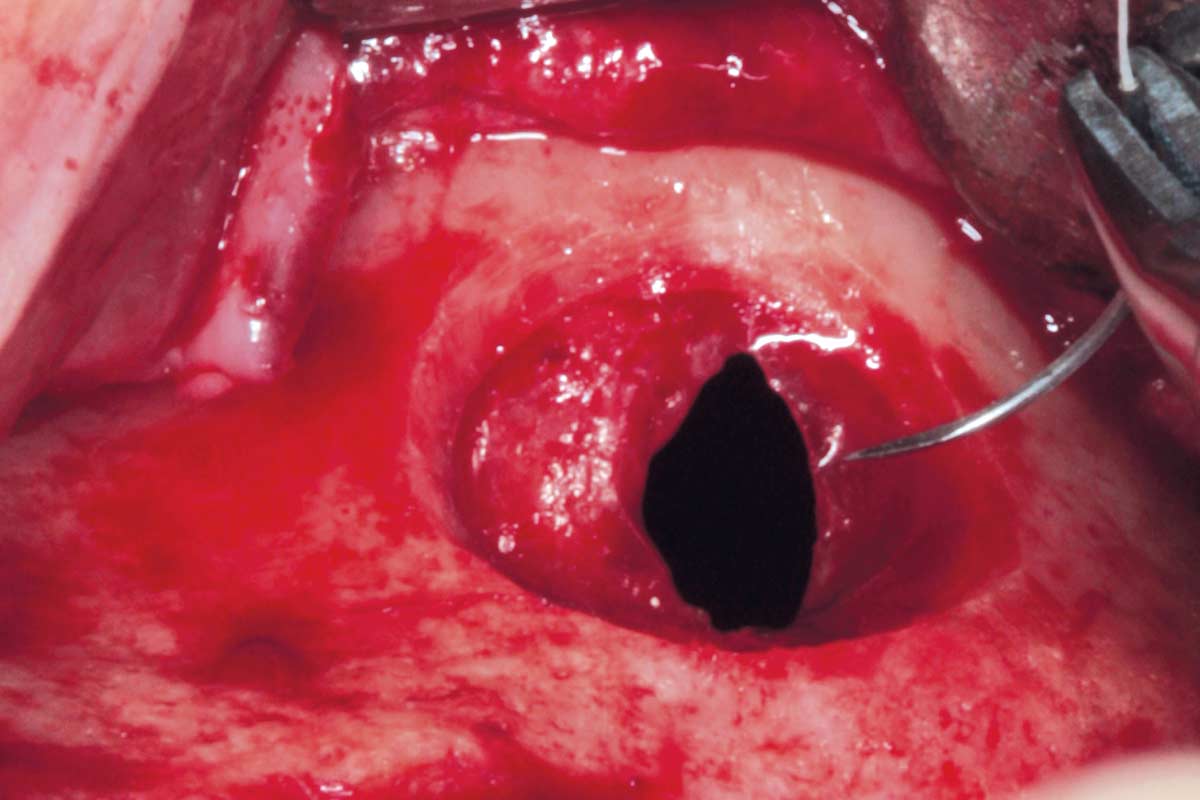

04/35 - Preparation of the lateral sinus window using piezosurgeryMaxillary sinus cyst removal using the Crocodile Technique and subsequent lateral sinus lift - Dres. C. Scognamiglio and A. Perucchi